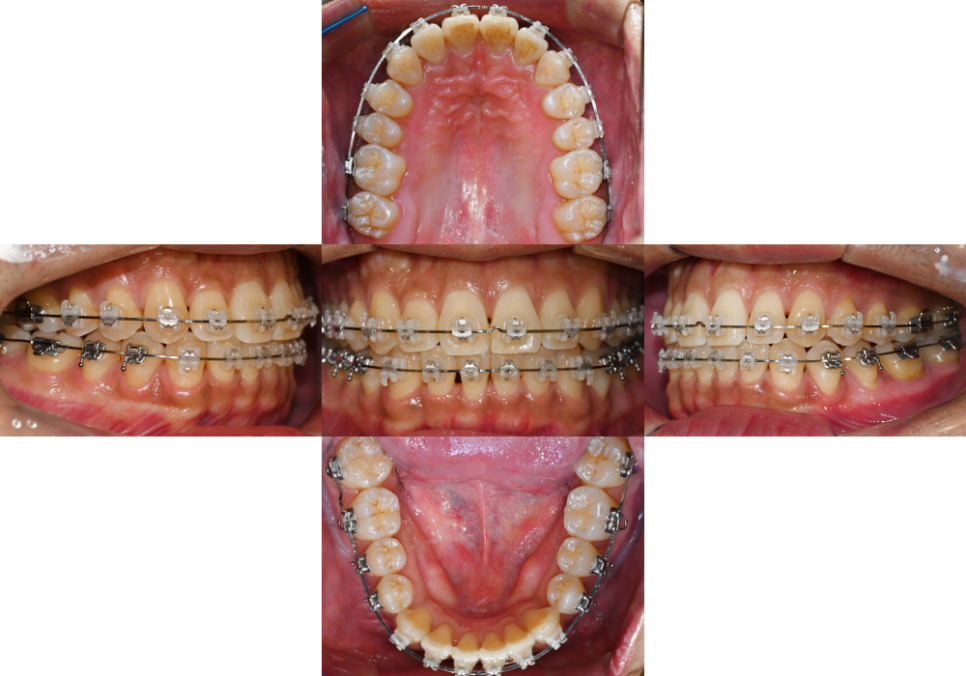

24.07.15

이러한 과정 덕분에

치열과 아래 악궁의 형태 개선이 된 것을

확인할 수 있었습니다.

치열이 어느 정도 올곧게 변하면서

치아 사이 공간이 나타난 것을

볼 수 있는데요.

이는 앞서 계획에서 말씀드렸듯이

치아 사이를 삭제하여

미세 조정을 하면서 맞출 수 있습니다.